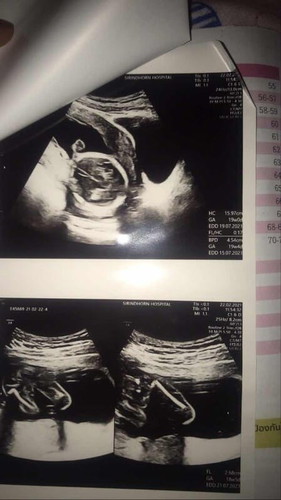

ช่วยดูเพศกันค่ะ

แบบนี้ผู้หญิงหรือผู้ชายคะใครดูเป็นบ้างช่วยดูหน่อยค่ะ🙏

รูปที่2 ลงมาข้างล่างซ้ายมือ เห็นเหมือนระหว่างขา เป็นจู๋ยื่นออกมา แต่ถ้าให้มั่นใจถามหมอเลยดีกว่าค่ะ 😊😁